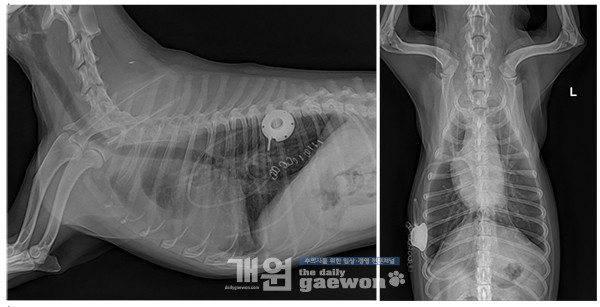

환자는 심장사상충 치료 이후 특별한 증상 없이 지내다 복부팽만과 기침 등을 나타내어 투약처방을 받았으나 반응이 없어 본원으로 내원하였습니다. 내원 시 검사해보니 심장사상충에 의한 비가역적 변화에 의한 심한 우심부전증으로 진단하였습니다. 환자의 전체적인 움직임이 크지 않고, 입원 시에 복수를 200ml전후를 매일 천자해서 일시적 배액장치를 장착하여 투약과 함께 복수관리를 하기로 결정하였습니다.